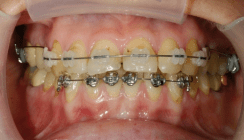

Ein Teilbogen, der in den Auxi­liary-Tube des Molarenbandes von 26 eingefügt worden war, initiierte durch entsprechende Biegungen, wie vorher beschrieben, die aktive Eruption des Eckzahnes (Abb. 15). Somit konnte zu diesem Zeitpunkt eine vollständige Bebänderung mit entsprechender Beeinträchtigung für das subjektive Empfinden, die Ästhetik und die Mundhy­gienefähigkeit vermieden werden. Nachdem der Eckzahn an seinen physiologischen Standort im Zahnbogen angenähert war, erfolgte zur Korrektur von Zahnfehlstellungen und Feineinstellung von 23 die vollständige Bebänderung (Abb. 16). Das nach der kieferorthopädischen Einstellung angefertigte OPG (Abb. 17) zeigt die achsengerechte Stellung aller Wurzeln in mesiodistaler Richtung und den physiologischen Alveolarknochenverlauf an 23. Die klinischen Bilder zeigen die Okklusion nach Abschluss der Behandlung. Es liegt eine stabile funktionelle Okklusion und ästhetisch ansprechende Gingivakontur mit gesundem Parodontalzustand an 23 vor (Abb. 18a–d). Als Retentionsgerät wurde ein Hawley-Retainer eingegliedert.